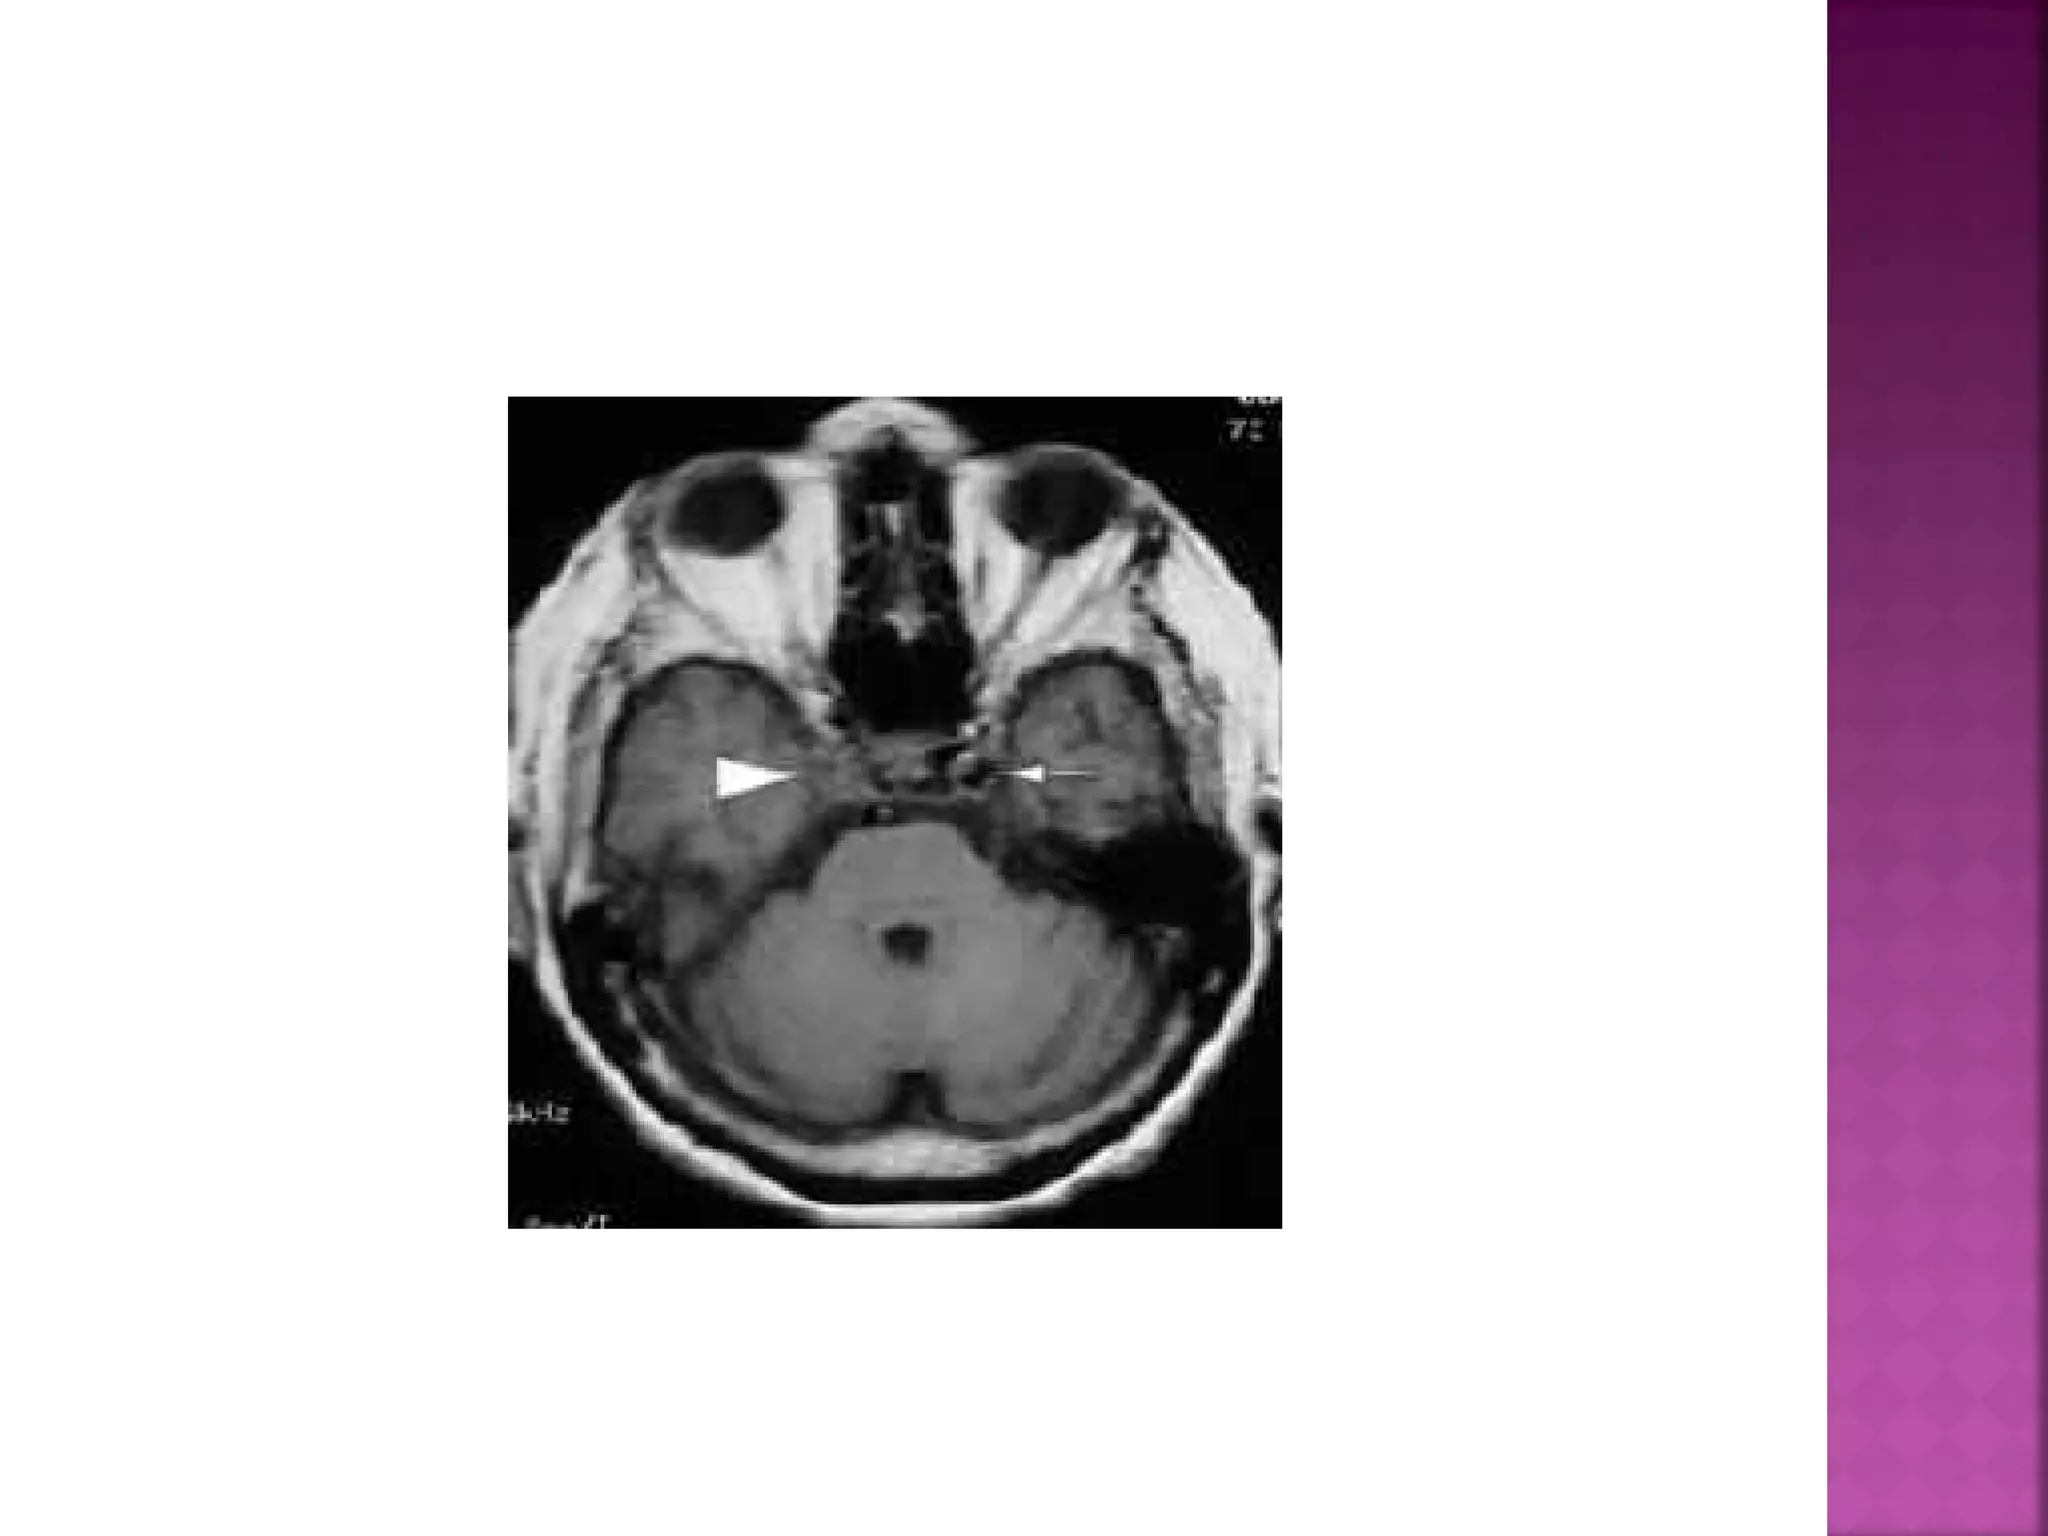

 The diagnosis isinfarction, because of the location (vascular territory of the middle cerebral artery (MCA) and because of the involvement of gray and white matter, which is also very typical for infarction.

 Obscuration of thelentiform nucleus, also called blurred basal ganglia, is an important sign of infarction. It is seen in middle cerebral artery infarction and is one of the earliest and most frequently seen signs. The basal ganglia are almost always involved in MCA-infarction.

 This refers tohypodensity and swelling of the insular cortex. It is a very indicative and subtle early CTsign of infarction in the territory of the middle cerebral artery. It has to be differentiated from herpes encephalitis.